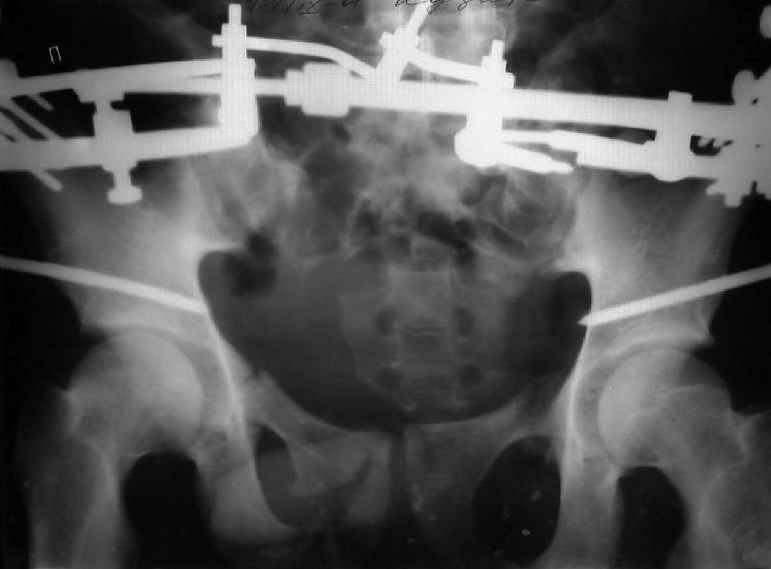

Уважаемые коллеги! Хотел-бы обсудить варианты лечения больной с застарелым переломом таза. Возраст 40 лет. Травма 11 месяцев назад. Главный травматолог Камчатского Военно-морского госпиталя Юрий Алексеевич Булахтин

У больного судя по всему вертикальная деформация таза. А каковы основные жалобы пациента и какие у него функциональные требования?

Для принятия решения об оперативном лечении и о его объеме, представляется целесообразным выполнение рентгенографии в проекции "inlet", а так же функциональных рентгенограмм стоя попеременно на правой и левой нижних конечностях (для определения нестабильности тазового кольца).